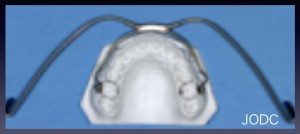

【1】ヘッドギア(EOA)

上顎前突「出っ歯」の改善を目的とする装置で、奥歯を遠心(後方)に送る装置です(写真下)。

上顎の成長抑制のほか、成長期の段階で上顎の奥歯を後方に動かしたり、歯列全体を後方へ移動させる治療を行う事が出来ます。歯や顎に適正な力をかけることで、顎の骨の成長コントロールや歯の移動を行います。へッドギアの装着方法は、上の奥歯(第一大臼歯)に装着した固定式の装置(バンド)に

フェイスボウと呼ばれる太いワイヤーをご自身で装着し、これをネックバンドと呼ばれるゴムで引っぱります。

口腔内の金属バンド以外は使用しない時に取り外し可能です。